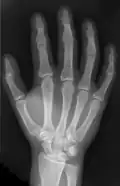

The intermetacarpal joints are in the hand formed between the metacarpal bones. The bases of the second, third, fourth and fifth metacarpal bones articulate with one another by small surfaces covered with cartilage. The metacarpal bones are connected together by dorsal, palmar, and interosseous ligaments.

• The dorsal metacarpal ligaments (ligamenta metacarpalia dorsalia) and palmar metacarpal ligaments (ligamenta metacarpalia palmaria) pass transversely from one bone to another on the dorsal and palmar surfaces.

• The interosseous metacarpal ligaments (ligamenta metacarpalia interossea) connect their contiguous surfaces, just distal to their collateral articular facets.